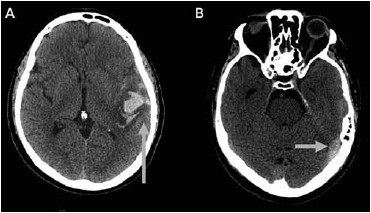

Homem, 60 anos, sem antecedentes prévios, foi admitido no pronto-socorro com quadro de afasia mista. Na admissão encontrava-se afebril, taquicárdico e pressão arterial de 210/103 mmHg. As imagens de tomografia de crânio realizadas estão a seguir. As setas indicam um sinal característico encontrado nas suspeitas de trombose venosa cerebral. Assinale a alternativa correta.

(Arquivo pessoal; imagem usada com autorização)